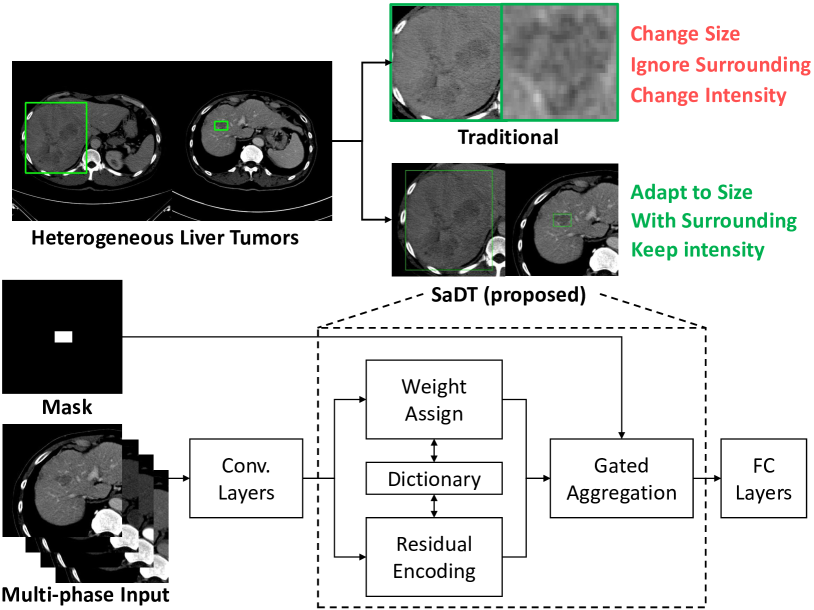

With the primary lesion \acpROI localized and filtered using the \acKSF of Sec. II-C, the next step is to differentiate them into \acHCC, \acICC, metastasis, or benign (which includes hemangioma, focal nodular hyperplasia, and adenoma). Standard object recognition based \acpCNN can serve this function, but texture-based approaches have experienced success [8, 9], particularly prior to deep learning. In this work, we propose to formulate the tumor characterization problem (visually classifying liver tumor subtypes) using an unstructured deep texture approach. For physicians, texture features clinically serve as important cues for assessing soft-tissue properties [24], especially when observing the changing \acCT intensities in the tumor site under different contrast phases. While it is theoretically possible to perform 3D texture modelling, the high inter-slice thickness of most \acpCT, e.g., mm in our data, is too coarse to capture texture. Instead, we apply a 2D deep texture learning workflow, adapting and enhancing the recent DeepTEN model [44] to create a \acfSaDT network. Using 2D models also allows us to use pretrained models, which is another key benefit. Fig. 6 depicts our \acSaDT model.

However, different from the standard texture learning scenarios, lesion sizes are heterogeneous across different cases (Fig. 6). The simple resizing seen in most texture learners is not optimal, since it alters the intrinsic physical resolutions of the \acCT. To address these spatial variations, we propose a new spatial adaptive aggregation that modifies (5) to

| (6) |